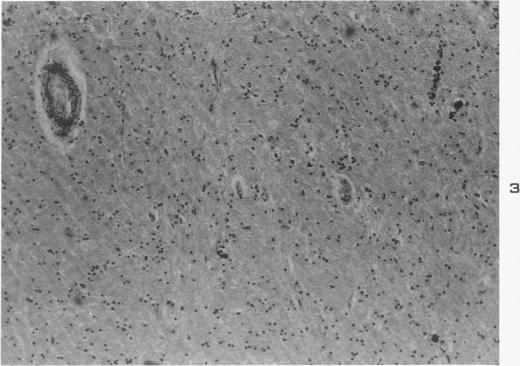

Histochemical demonstration of copper in a case of hepatolenticular degeneration.

Am J Pathol. 1955 May-Jun;31(3):545-53.

Histochemical demonstration of copper in a case of hepatolenticular degeneration.肝豆状核变性病例中铜的组织化学显示